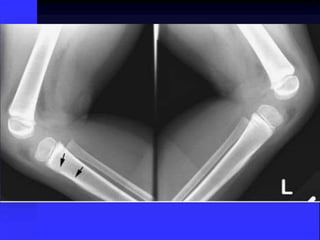

Physeal Fracture

Early stage of ossification Another variation of normal

Normal

Fracture